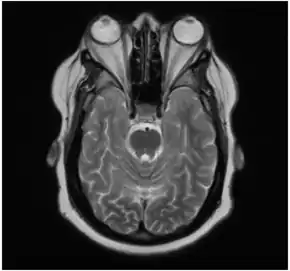

In the case of Graves' disease, the displacement of the eye results from abnormal connective tissue deposition in the orbit and extraocular muscles, which can be visualized by CT or MRI.[1]